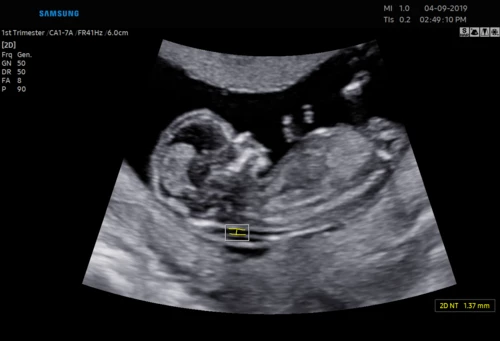

USG 3D dziecka w poradni ginekologicznej w Zambrowie –ocena NT, PAPP -A

Każdą kobietę w ciąży otaczamy kompleksową opieką, czuwając nad jej zdrowiem oraz prawidłowym rozwojem płodu. Podczas regularnych wizyt, zlecamy odpowiednie badania laboratoryjne. Korzystając z najnowszej generacji aparatu USG, przeprowadzamy bardzo dokładną diagnostykę obrazową – łącznie z USG 3D/4D płodu.

• Najnowsza generacja aparatu USG pozwala na przeprowadzanie dokładnej diagnostyki obrazowej, diagnostyki przepływów (Doppler).